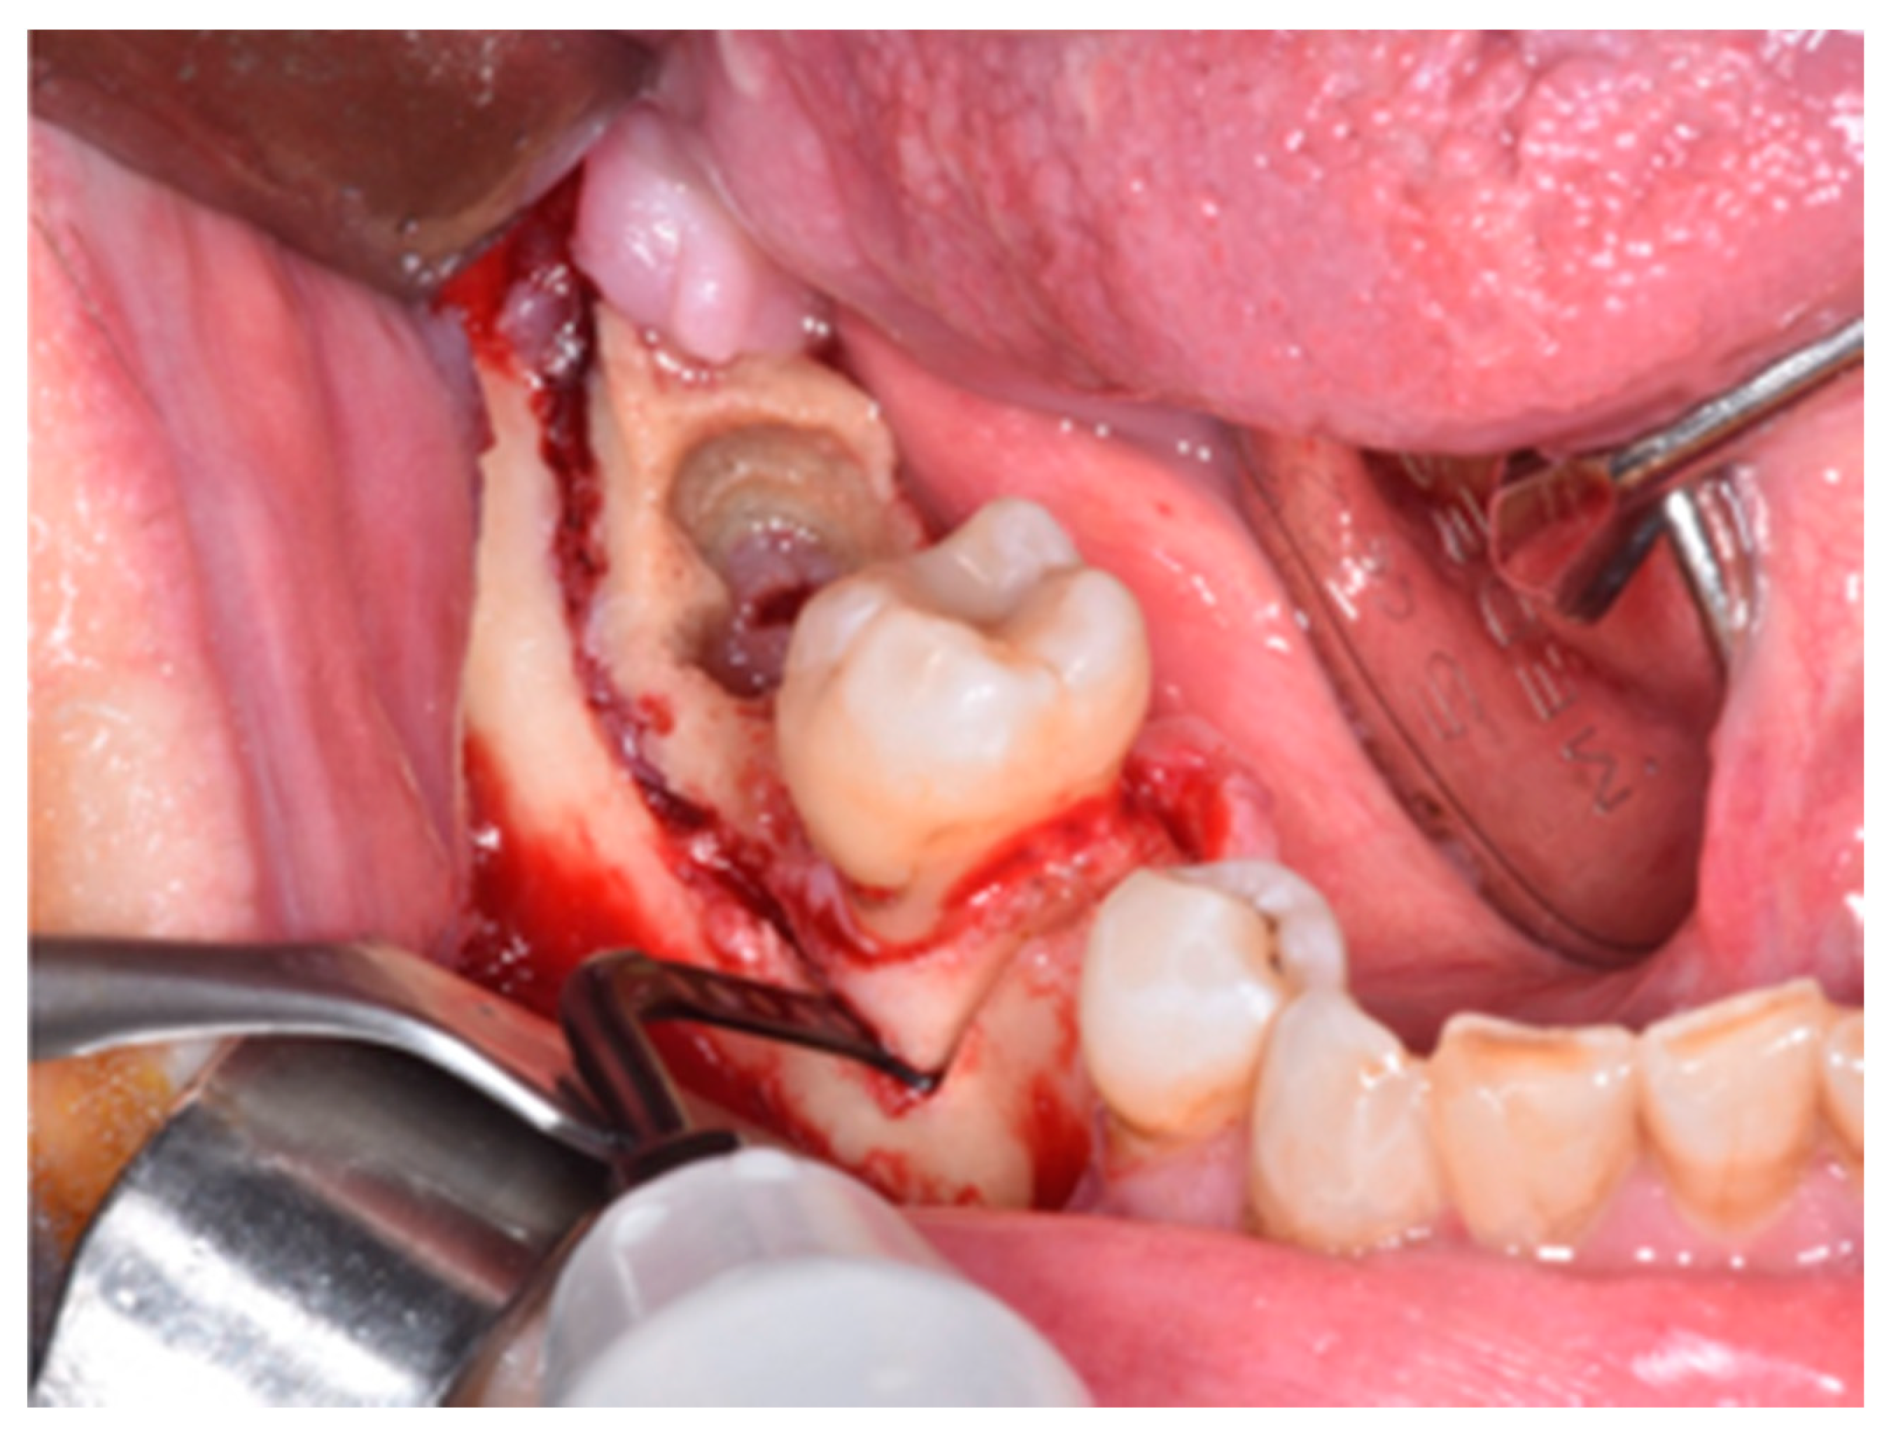

2. Materials and Methods

3. Results

4. Discussion